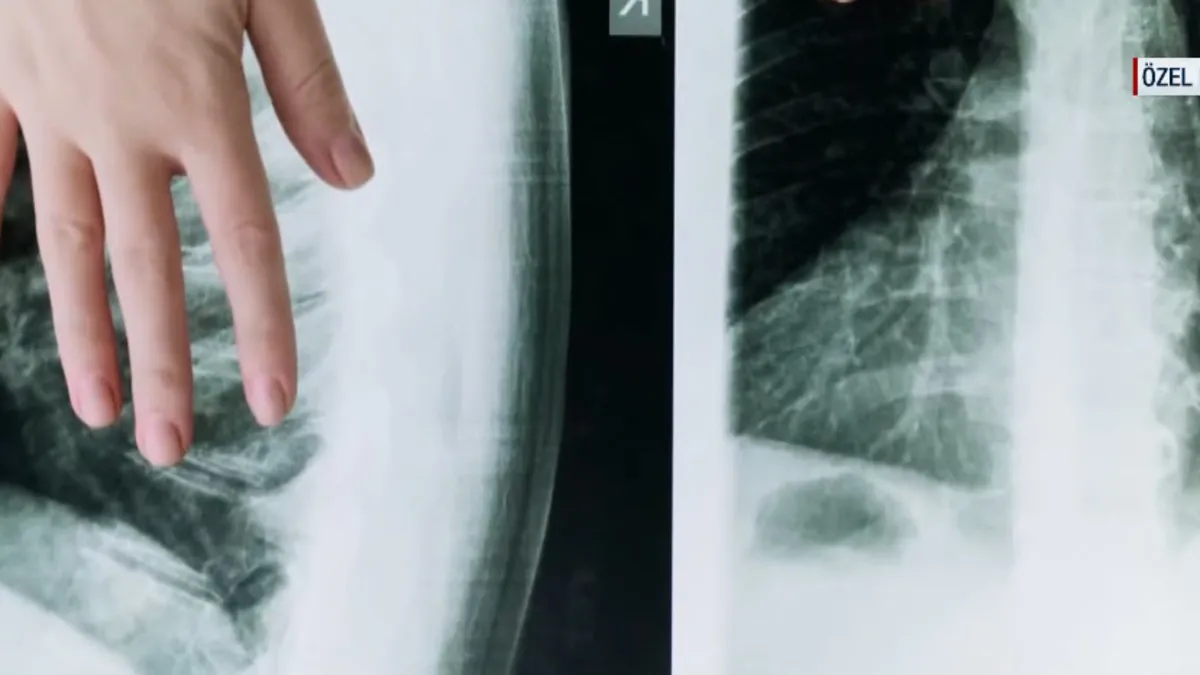

Türkiye'nin genel globaken verileri değerlendirildiğinde önde giden tümörler erkeklerde akciğer kadınlarda meme kanseri olarak görülüyor.

Uzmanlar "Türkiye'de en çok akciğer kanserini görüyoruz yıllar içinde. Erken tanı çok önemli bir yer teşkil etmekte. Kötü alışkanlıklardan uzak duralım, stresi azalmaya çalışalım." uyarısında bulundu.